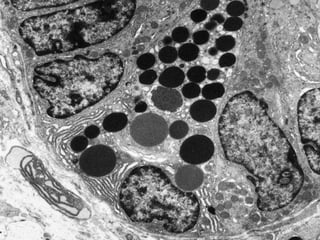

Este documento presenta imágenes microscópicas de diferentes tipos de tejidos y estructuras celulares teñidas con varios métodos histológicos. Incluye fotografías que muestran fibras de colágeno, elásticas y reticulares en diversos órganos, así como membranas basales y células especializadas de órganos como riñones, glándulas mamarias y próstata. El propósito es demostrar la aplicación de técnicas histológicas para visualizar componentes celulares y tej